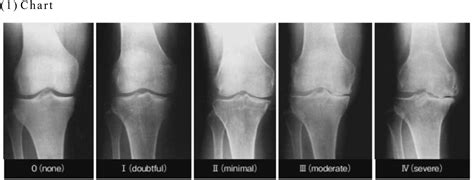

The Kellgren Lawrence Scale is the most widely utilized system for classifying the severity of knee osteoarthritis (OA) based on radiographic findings. Originally developed in 1957, this grading system analyzes X-ray images to look for specific signs of joint wear and tear, such as joint space narrowing, the formation of bone spurs (osteophytes), and structural deformities.

By assigning a grade from 0 to 4, medical professionals can communicate the extent of damage consistently. This standardization is vital for clinical research and patient care because it allows for a clear, objective measurement of how much a joint has deteriorated over time.

Breaking Down the Grades

The scale functions on a five-point system, where 0 represents a healthy joint and 4 represents severe, advanced disease. Below is a breakdown of how each grade is interpreted:

Grade Classification Description

Grade 0 None No radiographic features of osteoarthritis are present.

Grade 1 Doubtful Minute osteophytes of doubtful clinical significance.

Grade 2 Mild Definite osteophytes and possible joint space narrowing.

Grade 3 Moderate Multiple osteophytes, definite joint space narrowing, and some sclerosis.

Grade 4 Severe Large osteophytes, marked joint space narrowing, severe sclerosis, and bony deformity.